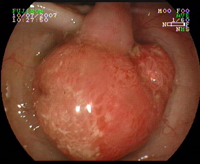

Polype sessile dysplasique